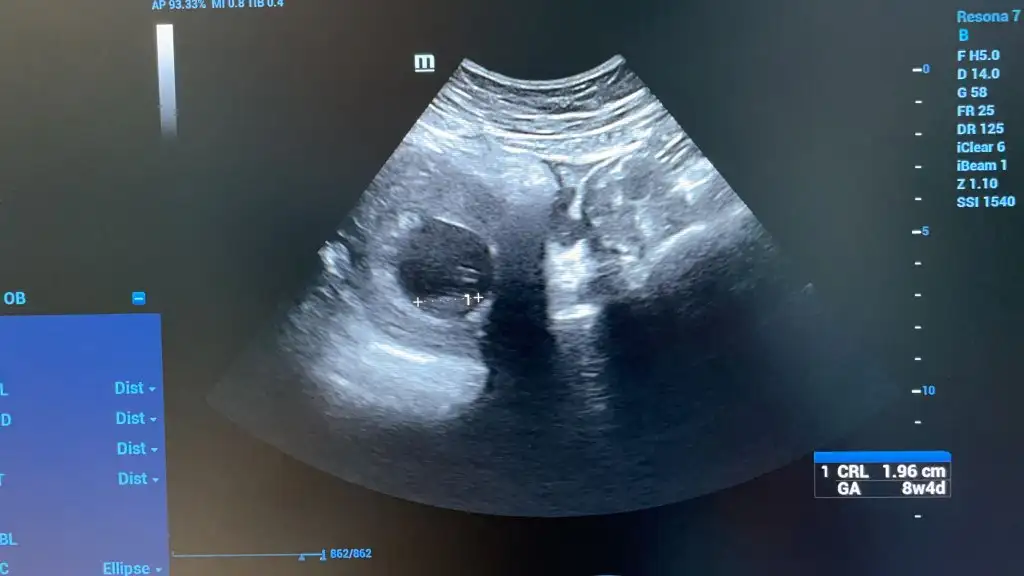

Bana da bakar misiniz ilki 6+4 vajinal diger ikisi 12+5 karindan cinsiyet belli degil henuz tahmin ederseniz sevinirim

Banada yorum yaparmısınız 7+1 alttan muane ile bakıldı kalp atıslarını duydumuz gün. Hiç farketmiyor cinsiyeti ama ramzi diye bişey duydum 🤗